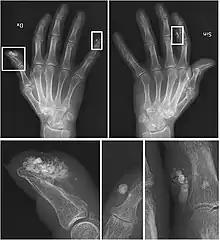

| CREST syndrome (calcinosis and sclerodactyly) | |

CREST causes thickening and tightening of the skin with deposition of calcific nodules ("calcinosis").

Though it is the most easily recognizable manifestation, it is not prominent in all patients. Thickening generally only involves the skin of the fingers distal to the metacarpophalangeal joints in CREST. Early in the course of the disease, the skin may appear edematous and inflamed. Eventually, dermal fibroblasts overproduce extracellular matrix leading to increased tissue collagen deposition in the skin. Collagen cross-linking then causes a progressive skin tightening. Digital ischemic ulcers commonly form on the distal fingers in 30-50% of patients.[3]